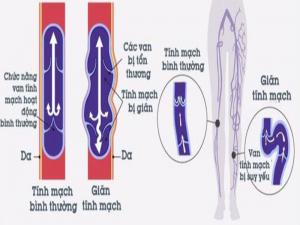

NGUYÊN NHÂN CỦA SUY TĨNH MẠCH MẠN TÍNH

Khiếm khuyết bẩm sinh hoặc mắc phải hệ thống van tĩnh mạch nông, sâu có thể dẫn tới CVI. Hoặc do suy giảm chức năng van tĩnh mạch do huyết khối như mô tả trong tam chứng Virchow (ứ máu tĩnh mạch, tăng động và tổn thương nội mạc). Tĩnh mạch bị dãn hiếm khi liên quan tới sự phát triển thành CVI. Hầu hết các trường hợp suy tĩnh mạch đều có liên quan tới trào ngược qua các tĩnh mạch nông.

CƠ CHẾ SINH LÝ BỆNH GÂY SUY TĨNH MẠCH

Nhiều cơ chế khác nhau góp phần làm suy yếu van tĩnh mạch nông.

- Thường gặp nhất là yếu thành tĩnh mạch bẩm sinh, tĩnh mạch giãn dưới áp lực bình thường dẫn đến suy tĩnh mạch thứ phát.